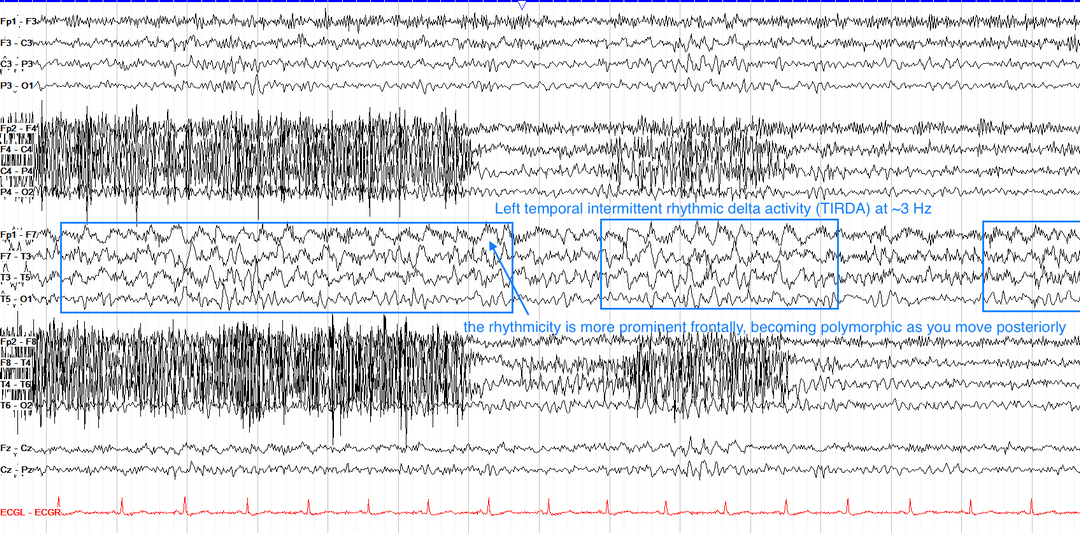

4.时间间歇性节律性δ活动(TIRDA)

本质是慢波,但高度提示颞叶癫痫(需结合其他癫痫样放电确认)。

区别于癫痫样放电:波形圆钝,无棘波成分,但可能演变为棘慢波。